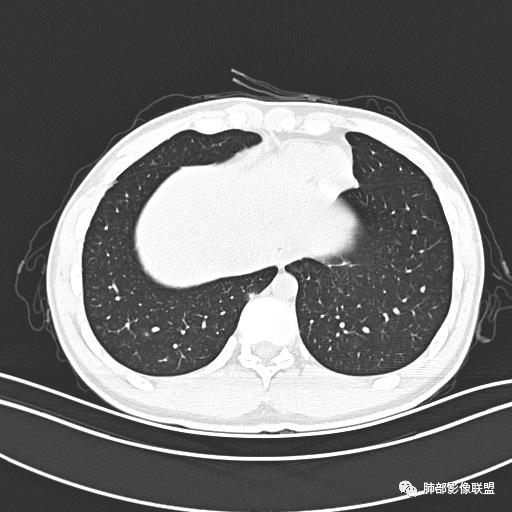

小强:青年,发热,皮疹;双肺散在结节,周围磨玻璃,点晕征,疱疹病毒感染,鉴别荚膜组织胞浆菌,结核。 大雄:青年,急性起病,发热伴全身皮疹2天,抗病毒治疗体温有下降。双肺随机分布大小不等类圆结节,“点晕征”。考虑水痘-疱疹病毒(VZV)血播询问接触史,查体皮疹分布以及形态基本可诊断。 王开金江津中心医院呼吸科:青年男性,起病急,病程短,以发热,皮疹为首发症状,感染指标以单核细胞升高为主,胸部ct双肺多发结界,周围有晕,点晕表现,随机分布,同意於老师意见,水痘疱疹病毒血流感染累及肺。 王秀仙:双肺多发大小不等结节,周围有晕,边缘模糊,呈点晕征表现。青年,急性起病,发热伴全身皮疹2天,抗病毒治疗体温有下降。考虑疱疹病毒。鉴别荚膜组织胞浆菌。 傅昌瑜:19岁男性,发热、全身皮疹2天,单核细胞增高,双肺多发结节,结节边缘见边界不清磨玻璃影。点晕征+发热、全身皮疹+单核细胞增高——考虑水痘-带状疱疹病毒肺炎。 一切∮随缘:年轻男性,发热,皮疹两天,实验室,CRP,PCT增高,影像:双肺多发散在磨玻璃结节,边界欠清,大小不等,呈点晕征改变,以血管束周围分布为主,局部血管束略增粗,其它无明显改变,考虑:1:病毒性肺炎(水痘疱疹病毒?不知道皮肤有无改变)2:真菌(组织胞浆菌,血管侵袭性肺曲霉)3:GPA4:寄生虫(实验室没有看到嗜酸细胞增高) 赵山河:双肺散在结节,周围有晕,边缘模糊,呈点晕征表现。青年,急性起病,发热伴全身皮疹2天,抗病毒治疗体温有下降。考虑水痘—疱疹病毒感染。洪桥爱:青年男性,发热、皮疹2天,伴瘙痒,皮疹于面部首发,之后进展至全身,虽然没有对皮疹进行描述,但是从出疹时间及皮疹进展情况,伴瘙痒,应该就是个水痘患者;CT提示双肺随机分布结节影,部分结节伴有边界不清晕征,考虑水痘血播肺。 刘强:年轻男性,急性起病,皮疹,发热,抗感染治疗体温下降,说明有效。影像表现为散在点晕征,感染类疾病谱(疱疹病毒,真菌,结核),结合年龄,皮肤皮疹,考虑水痘-疱疹病毒性肺炎。 小兜:男性,19岁,发热皮疹两天,颜面部至全身,CRP,降钙素及单核增高。CT示双肺散在小结节,周围伴磨玻璃影,点晕征,考虑为水痘-带状疱疹病毒(varicella-zoster virus,VZV)肺炎 必有路:青年,皮疹+发热+“点晕征”→水痘-疱疹病毒(VZV) 许慧良:青年男性患者,发热、皮疹2天,体温最高38.5℃,第3天皮疹扩展至全身,伴瘙痒,胸部CT:双肺多发随机分布的小结节,结节周边见边界模糊的晕征,考虑水痘病毒感染流心明智:男,19,急性起病,发热伴全身皮疹2天。出疹顺序头→全身,抗病毒有效。胸部CT:两肺多发大小不等类圆形实性小结节影,随机分布,结节周围环绕GGO,边界模糊,呈点晕征。出疹特点是关键,未提示。考虑:血播病毒性肺炎,水痘-疱疹病毒?麻疹?鉴别荚膜组织胞浆菌、TB、血管炎、寄生虫等。 浪迹天涯:病灶多为5-10mm大小结节,结节周围可见磨玻璃样的晕环,常多发,可分布于肺内任何区域,考虑水痘—带状疱疹病肺炎如果短时间内有新的一个区域浸润,更加能说明,